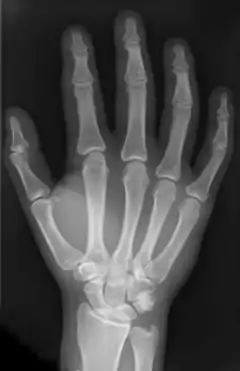

![]() Рентгенографія кисті людини | |